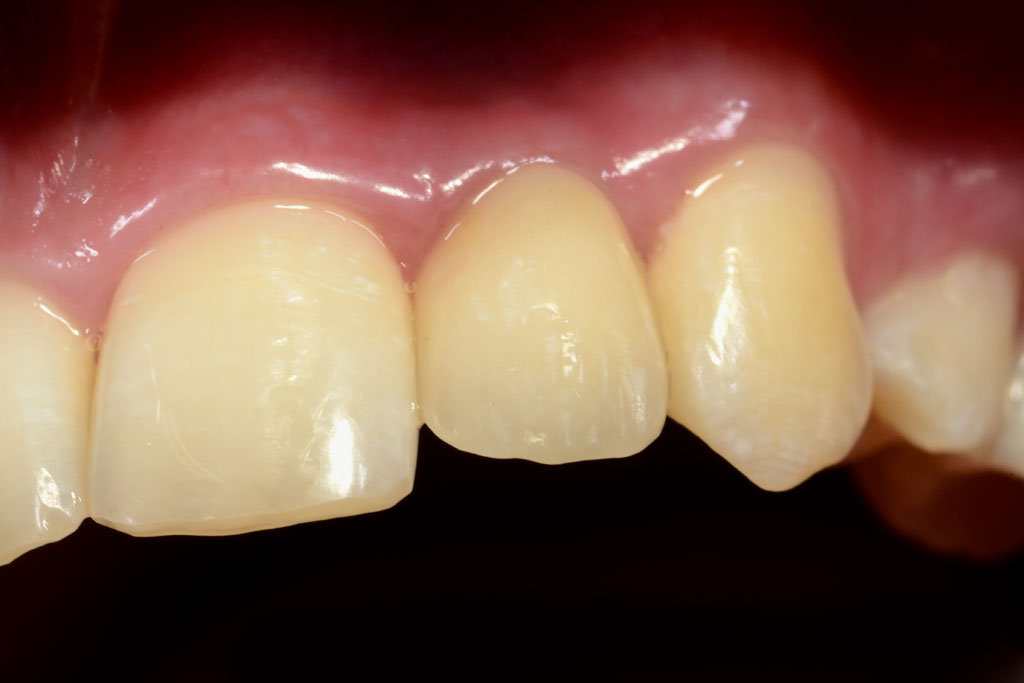

Die Nichtanlage der seitlichen oberen Schneidezähne und der zweiten unteren kleinen Backenzähne (Prämolaren) ist relativ häufig.

Wir verfügen über eine jahrzehntelange Erfahrung in der kieferorthopädischen Vorbehandlung, Implantologie und der prothetischen Versorgung von Nichtanlagen, sowie der Chirurgie und der Einordnung von verlagerten bleibenden Zähnen ohne den Einsatz von Implantaten.